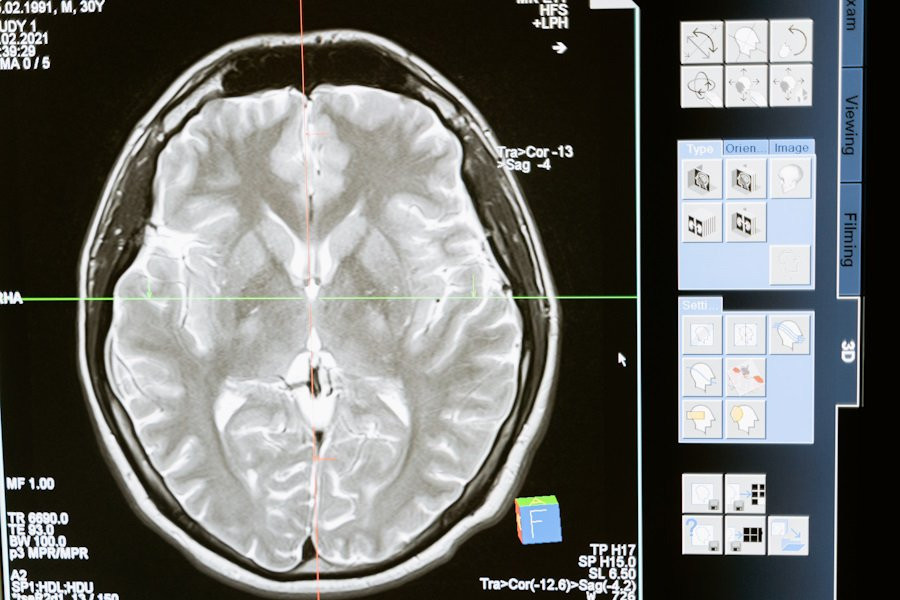

Нейрофизиологи ИВНД РАН представили уникальную технологию, которая обещает революционизировать лечение глиобластомы головного мозга - одной из наиболее агрессивных форм рака, сообщает издание "РГ".

Метод направлен на преобразование опухолевых клеток в зрелые нейроны, что приводит к уменьшению и агрессивности опухоли. Ученые объясняют, что технология основана на использовании специальных веществ, которые приостанавливают деление опухолевых клеток и стимулируют их созревание.